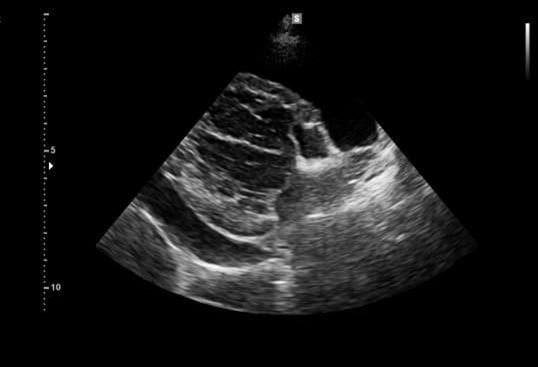

De echo thorax gemaakt door onze specialist diagnostische beeldvorming Susanne Boroffka, liet ernstige pericard overvulling zien met compressie van het rechter atrium. Geen duidelijke tumor zichtbaar maar kan dat helaas niet uitgesloten worden.